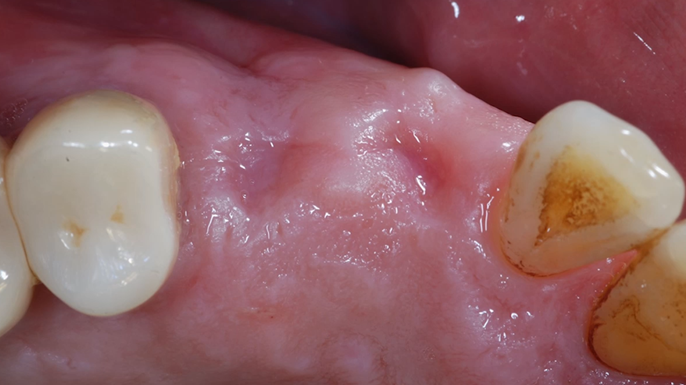

Clinical case: R2GATE GUIDE surgery with GBR

- Courtesy of Dr. Kwang Bum Park, Korea -

Keywords

Dr. Kwang Bum Park, digital guided surgery, bone regeneration, maxillary posterior, #13, #14, guided surgery, GBR, AnyRidge, i-GEN, Mega-Oss, R2GATE, R2GATE Full surgical kit